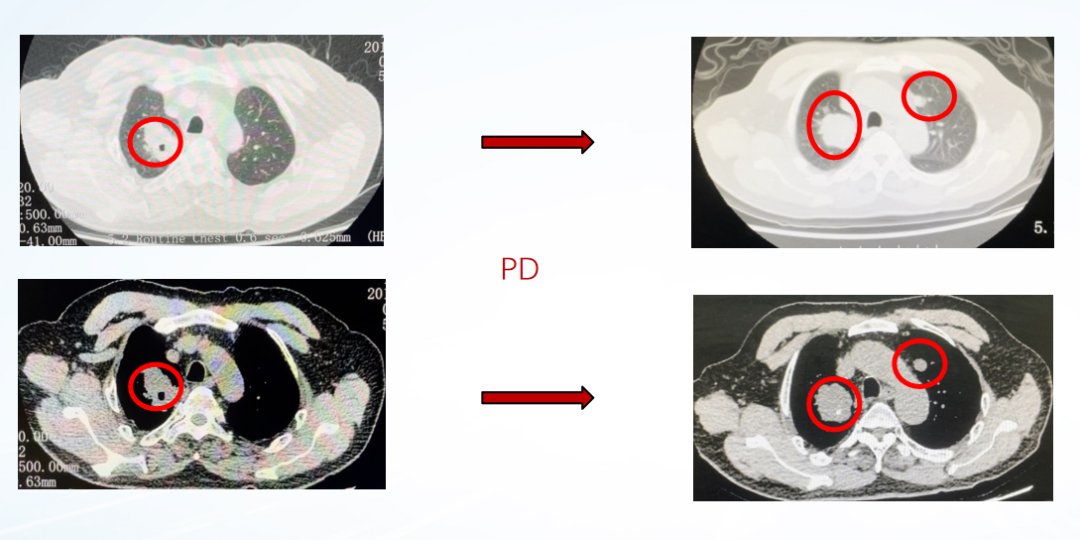

影像学评估:

图22、呋喹替尼治疗期间,患者肺部转移灶胸部增强CT评估情况:左(2020-10-23)、中(2021-05-27)、右(2021-07-06)

疾病进展:2021年8月,患者出现咳胸闷,咳嗽。胸部CT提示双肺转移瘤相仿,右侧支气管内多发软组织密度影。

图24、胸部增强CT显示支气管内新增转移病灶:左(2021-07-06)、右(2021-08-31)